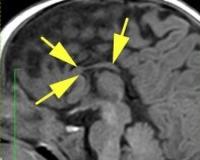

• КТ головного мозга. С помощью компьютерной томографии определяют широко расставленные передние рога, приподнятое положение третьего желудочка, параллельный ход медиальных стенок боковых желудочков. КТ выполняется в рамках послеродовой диагностики.

• МРТ головного мозга. Для наиболее точной визуализации степени агенезии или гипоплазии мозолистого тела новорожденному проводят трехплоскостную магнитно-резонансную томографию. В зависимости от показаний беременным может быть рекомендована МРТ для исключения сопутствующих нарушений ЦНС, несовместимых с жизнью.